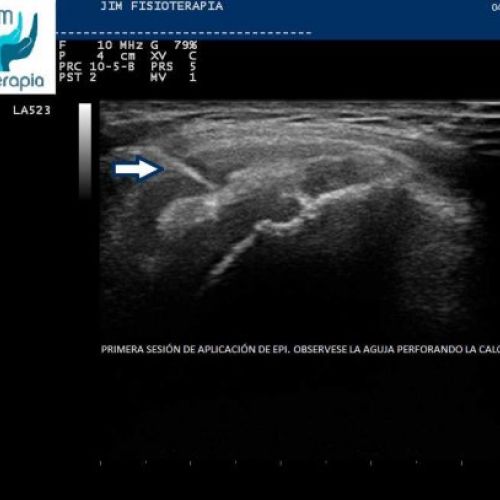

Tratamiento de epicondilitis con EPI®

EPI® Fisioterapia en Madrid para el tratamiento de la epicondilitis